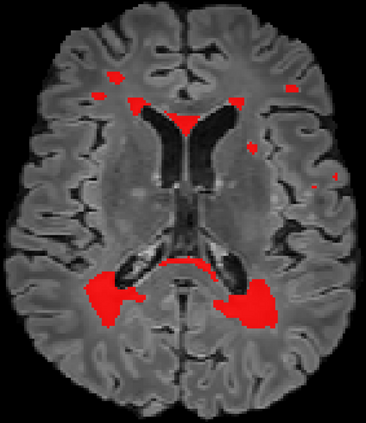

Assessment of lesions and their longitudinal progression from brain magnetic resonance (MR) images plays a crucial role in diagnosing and monitoring multiple sclerosis (MS). Machine learning models have demonstrated a great potential for automated MS lesion segmentation. Training such models typically requires large-scale high-quality datasets that are consistently annotated. However, MS imaging datasets are often small, segregated across multiple sites, with different formats (cross-sectional or longitudinal), and diverse annotation styles. This poses a significant challenge to train a unified MS lesion segmentation model. To tackle this challenge, we present SegHeD, a novel multi-dataset multi-task segmentation model that can incorporate heterogeneous data as input and perform all-lesion, new-lesion, as well as vanishing-lesion segmentation. Furthermore, we account for domain knowledge about MS lesions, incorporating longitudinal, spatial, and volumetric constraints into the segmentation model. SegHeD is assessed on five MS datasets and achieves a high performance in all, new, and vanishing-lesion segmentation, outperforming several state-of-the-art methods in this field.